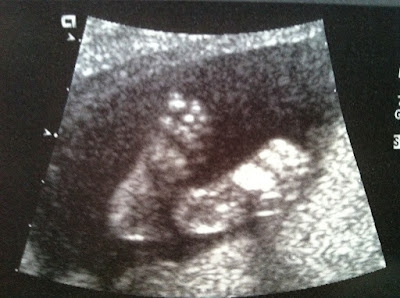

![]() |

| Baby Girl feet! |